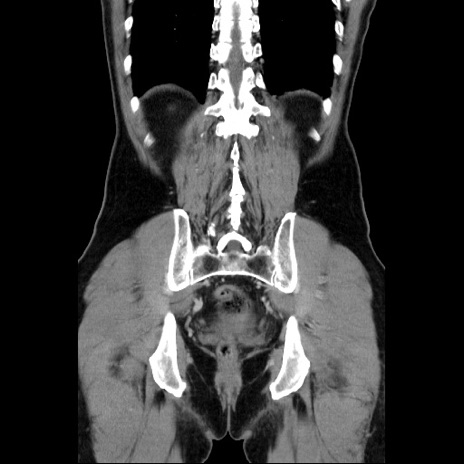

症例34(冠状断像)

【症例】60歳代 男性

【主訴】右鼠径部膨隆

【現病歴】1年程前より右鼠径部膨隆あり。自己にて還納可能だったため放置していた。3時間前より右鼠径部の脱出を認め、還納困難となり受診。

【既往歴】高血圧

【身体所見】右鼠径部に小児頭大の膨隆あり。弾性硬であり、用手還納は困難。左鼠径部にも膨隆を認める。脱出はなし。